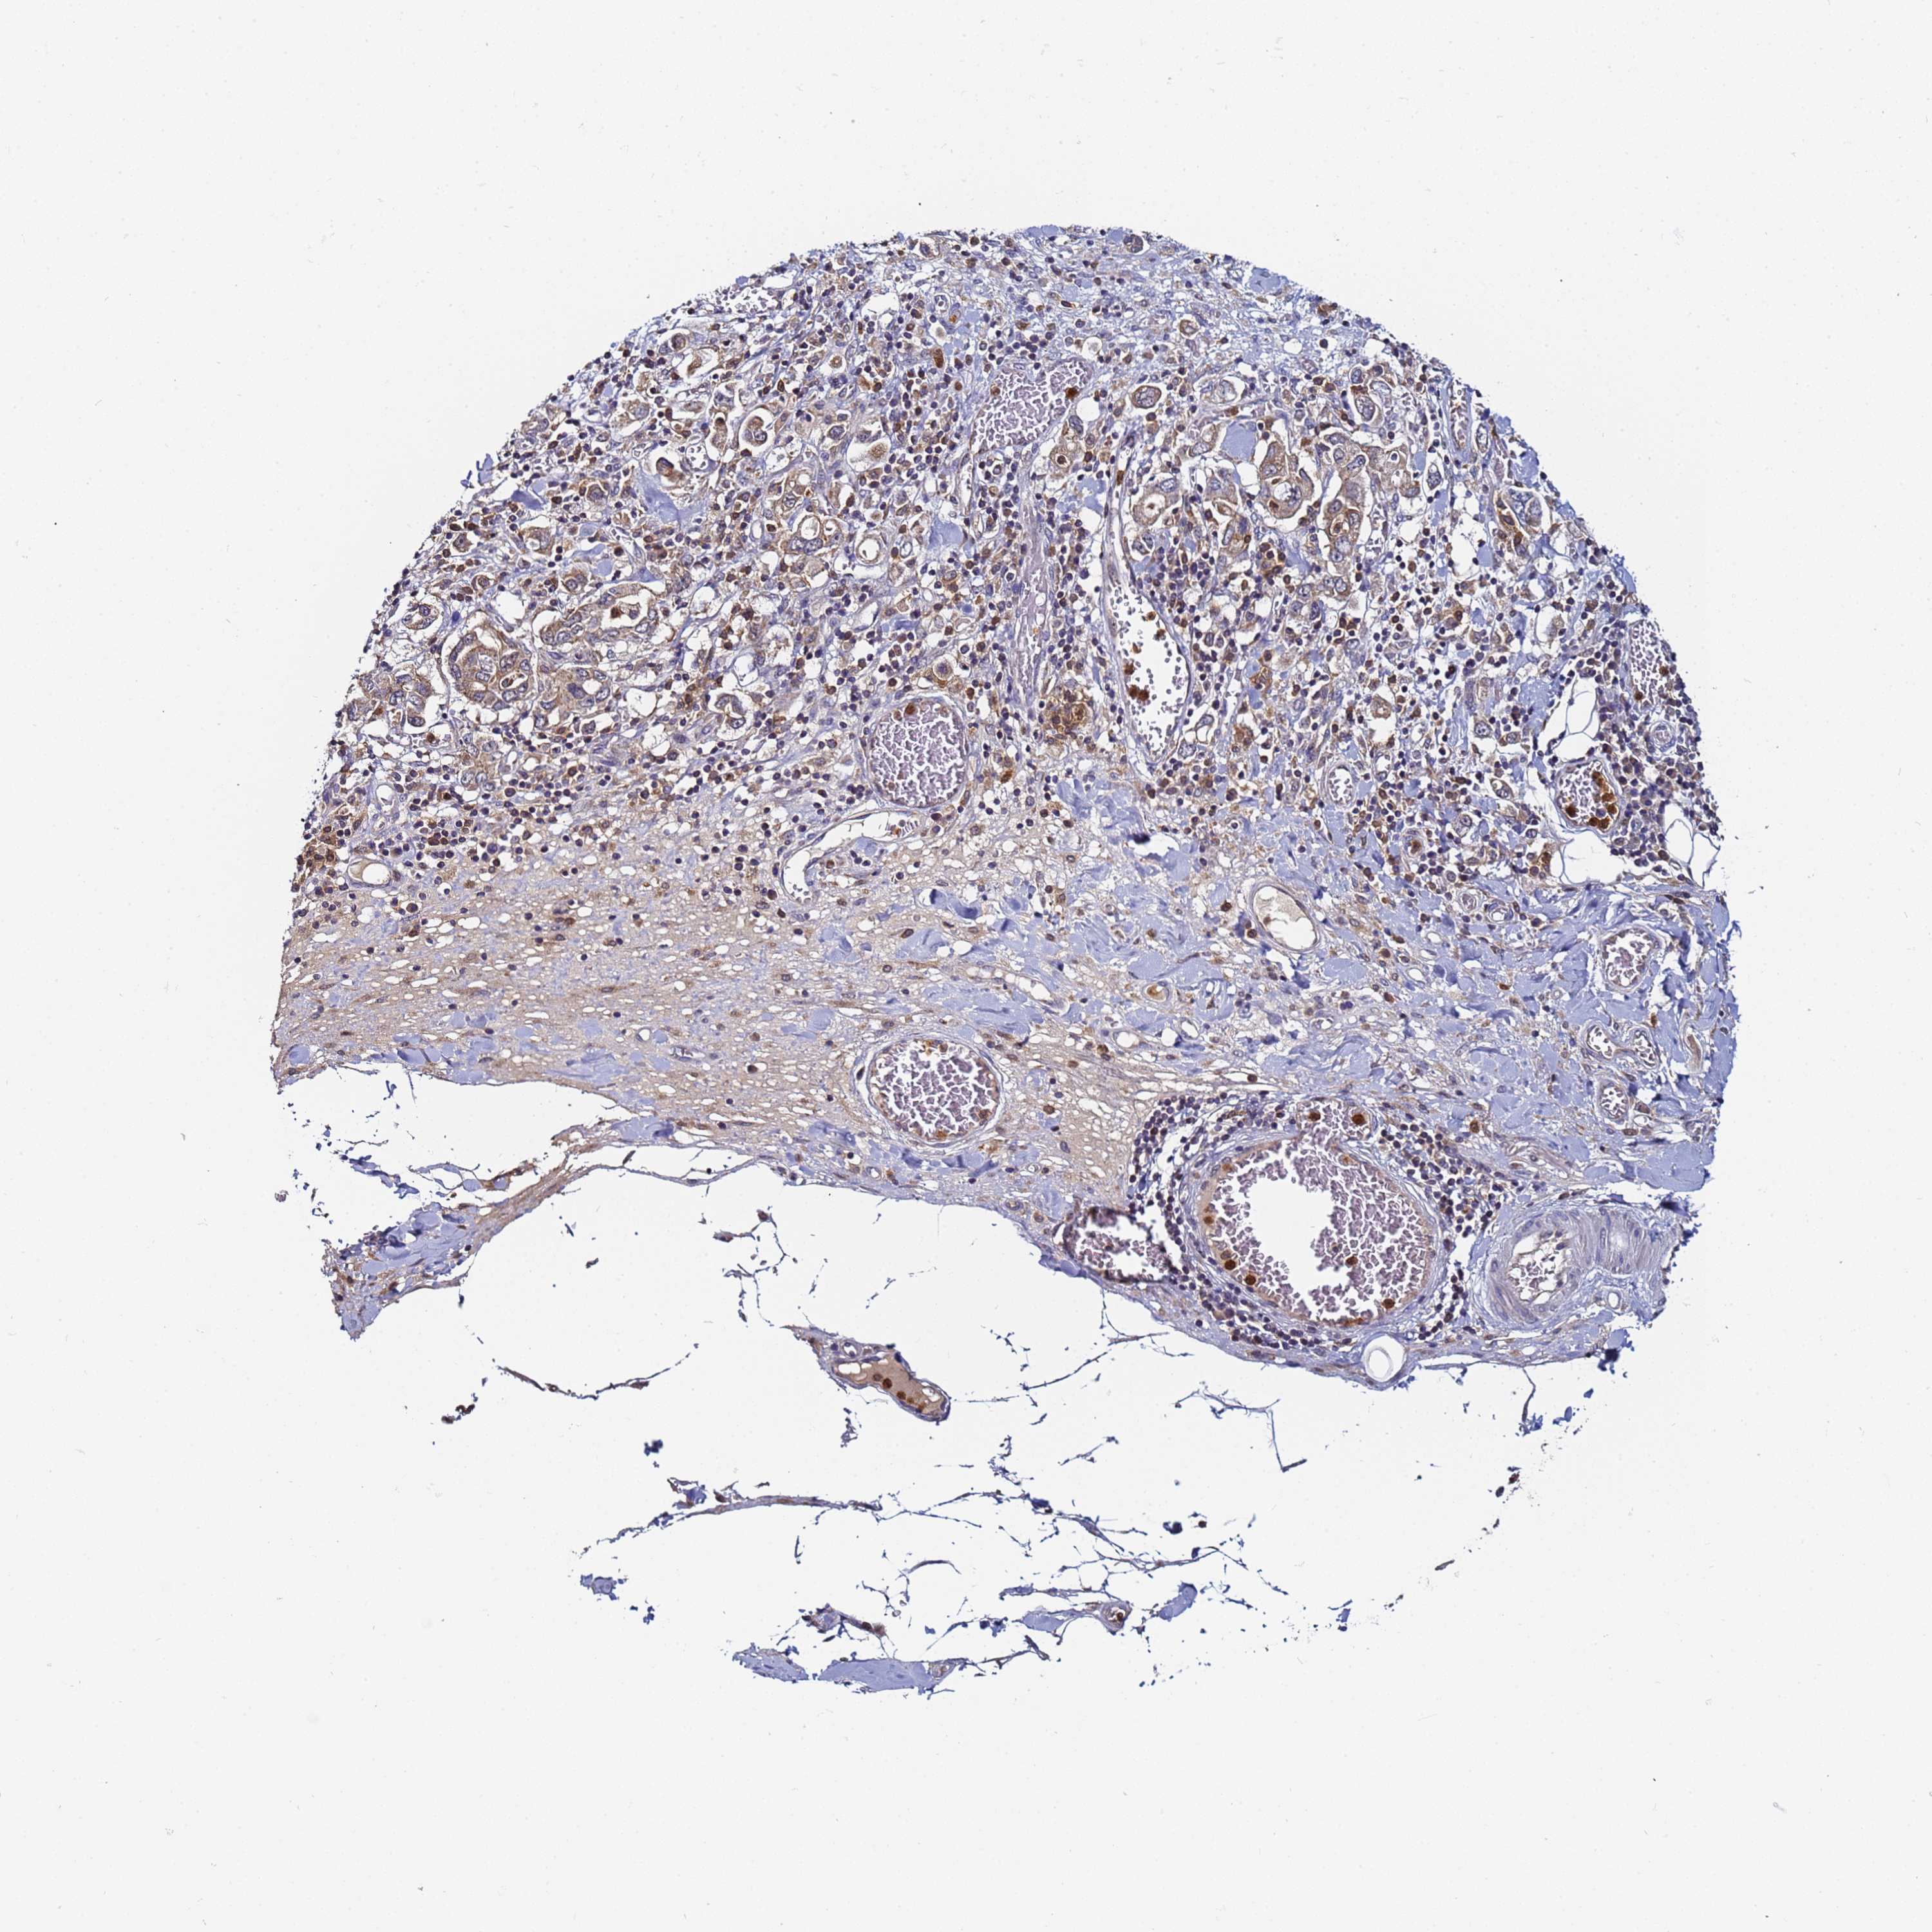

STOMACH CANCER - Protein expressioni

A mouse-over function shows sample information and annotation data. Click on an image to view it in a full screen mode. Samples can be filtered based on level of antibody staining by selecting one or several of the following categories: high, medium, low and not detected. The assay and annotation is described here.

Note that samples used for immunohistochemistry by the Human Protein Atlas do not correspond to samples in the TCGA dataset.

Antibody stainingi

Antibody staining in the annotated cell types in the current human tissue is reported as not detected, low, medium, or high, based on conventional immunohistochemistry profiling in selected tissues. This score is based on the combination of the staining intensity and fraction of stained cells.

Each image is clickable and will lead to virtual microscopy that enables deeper exploration of all samples and also displays staining intensity scores, fraction scores and subcellular localization as well as patient and tissue information for each sample.

Antibody HPA045052

Staining

High

Medium

Low

Not detected

Intensity

Strong

Moderate

Weak

Negative

Quantity

>75%

75%-25%

<25%

None

Location

Nuclear

Cytoplasmic/membranous

Cytoplasmic/membranous,nuclear

Adenocarcinoma, NOS